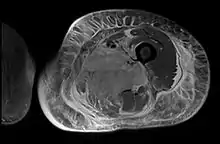

Creatine kinase may be normal or increased probably depending upon the stage of the condition when sampling is undertaken. ESR is elevated. Planar X-ray reveals soft tissue swelling and may potentially show gas within necrotic muscle, Bone scan may show non specific uptake later in the course. CT shows muscle oedema with preserved tissue planes (non-contrast enhancing). MRI is the exam of choice and shows increased signal on T2 weighted images within areas of muscle oedema. Contrast enhancement is helpful but must be weighed against the risk of Nephrogenic Systemic Fibrosis as many diabetics have underlying chronic kidney disease. Arteriography reveals large and medium vessel arteriosclerosis occasionally with dye within the area of tissue infarction. Electromyography shows non specific focal changes.

Axial fat suppressed post gadolinium contrast enhancement MRI image showing absent enhancement in the left thigh adductor muscles centrally indicating necrosis in diabetic myonecrosis.